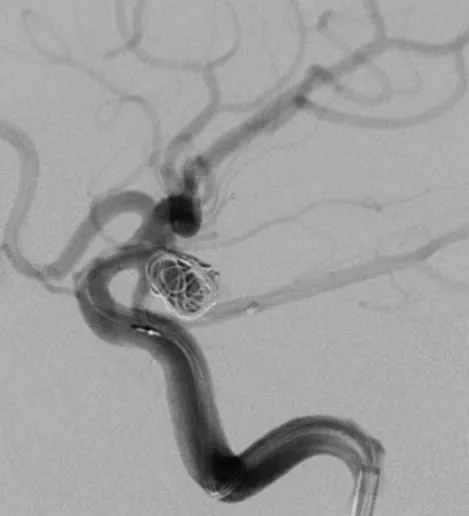

释放后的造影。突入颈内动脉和后交通动脉内的弹簧圈被压入瘤体内

继续填塞,后面就简单了。最后的结果,一共用了四枚弹簧圈,栓塞致密,瘤体及破口都不显影了

顺利完成手术。几点体会:1、支架要选用Enterprise或LVIS jr,好定位。2、支架末端够用就行,不能留得太长。3、弹簧圈不要先解脱,支架释放成功再解脱,一旦失败还有余地。4、推导管的时候要拽着支架推送杆,不要让支架提前意外解脱了。5、颈内动脉瘤颈以远太细或有狭窄的不建议。6、缺点是技术稍显复杂,优点是能很好的将瘤颈填致密,难度不大,适合的病例可以选择。在此感谢各位长期指导我的教授及专家。感谢冯雷教授的经验分享。